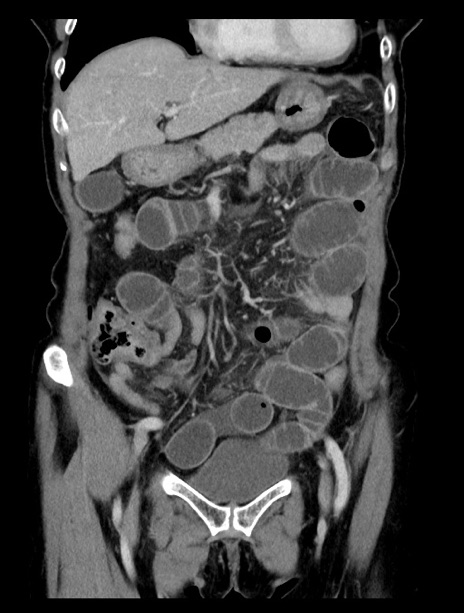

症例23(冠状断像)

【症例】70歳代女性

【主訴】下腹部痛・嘔吐

【現病歴】2日前より腹痛あり。昨日嘔吐あり。症状改善しないため来院。

【既往歴】胃GISTに対して胃部分切除後。

【身体所見】BT 37.1℃、BP 128/77mmHg、腹部:平坦・軟、下腹部に圧痛あり。

【データ】WBC 10200、CRP 0.31

横断像